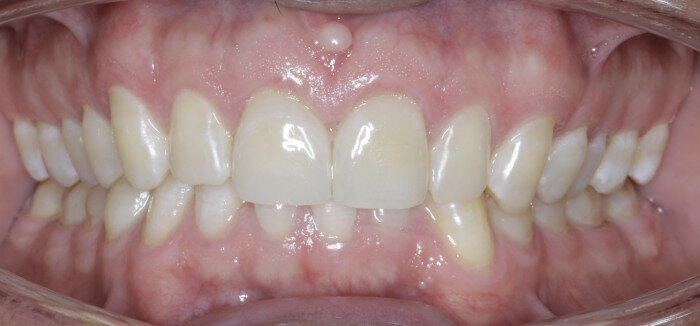

The anterior gummy smile The anterior gummy smile is one in which the patient shows excess gingival display from maxillary canine to maxillary canine (Figs. 4 & 5, beginning of treatment). This takes into account the ideal crown shape and size, where the patient has true anterior maxillary excess and is not just in need of a gingivectomy or crown lengthening procedure. To best determine if gummy smile treatment is needed in the anterior, the authentic smile photograph is used, alongside measurement of the incisor display at rest. If the resting incisor display is greater than threequarters in the adult patient without altered passive eruption, gummy smile treatment is needed. These cases are treated using two TADs placed between tooth #13 and #12 or between #22 and #23 using a 1.6 × 6.0 mm TAD. If slight posterior impaction is desired, bite turbos with Triad Gel (Dentsply Sirona) are placed on teeth #37 and #47 and squeezing exercises used to impact posterior molars engaging the posterior fibres of the temporal muscles (60 squeezes six times per day).

Fig. 4

Fig. 5